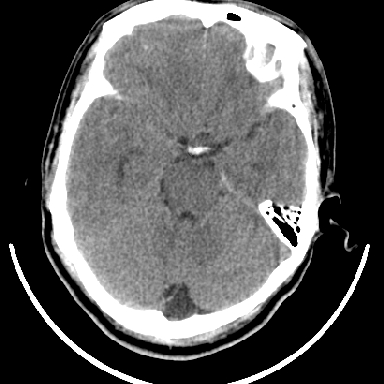

考虑高血压性脑出血,依据:

1是高血压性脑出血的好发部位,形态呈肾形,是高血压性脑出血的常见形状

2增强时占位效应加重了,考虑出血还没有停止

3病灶周围水肿不是太厉害,一般肿瘤出血水肿多非常明显

4病灶周围的‘软组织’影没有明显的强化

5至于脑血管畸形引起的出血,暂时没有看到明显的畸形血管影,也不太支持

支持右侧基底节脑出血

右侧基底节区脑出血.

支持右侧基底节区(主要为外囊区)原发性脑出血。